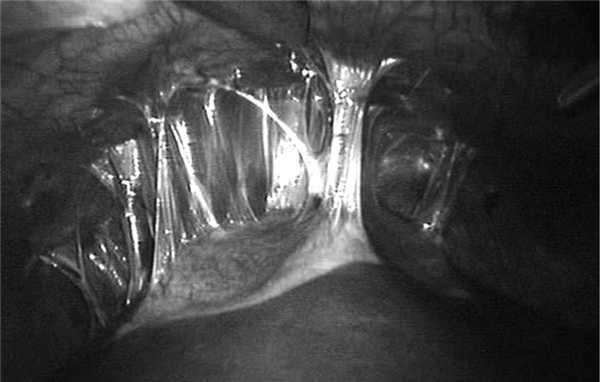

Протокол операции. Пневмоперитонеум 10 мм рт.ст. Порт для видеолапароскопа (порт № 1) установлен в верхней точке Калька. При осмотре брюшной полости обнаружены единичные сформировавшиеся спайки сальника с дном желчного пузыря. Рыхлые и плотные спайки с диафрагмой купола кисты на передней поверхности 5—7-го сегментов печени (рис. 3). Киста багрового цвета, размерами 6×8 см. При инструментальной пальпации киста не напряжена. В малом тазу серозный выпот объемом не более 100 мл.

Рис. 3. Лапароскопия: киста 5—7-го сегментов печени при состоявшемся прорыве в брюшную полость. Рыхлые спайки с диафрагмой и спавшаяся киста.

При рассечении спаек в области 7-го сегмента выявлена линейная трещина в перикистозной ткани печени длиной 4 см и шириной 0,25 см, в котором просматривается белесовато-серая кутикула эхинококковой кисты. В области разрыва перикистозной ткани небольшие фибриновые слизеподобные наложения и рыхлые спайки с диафрагмой.